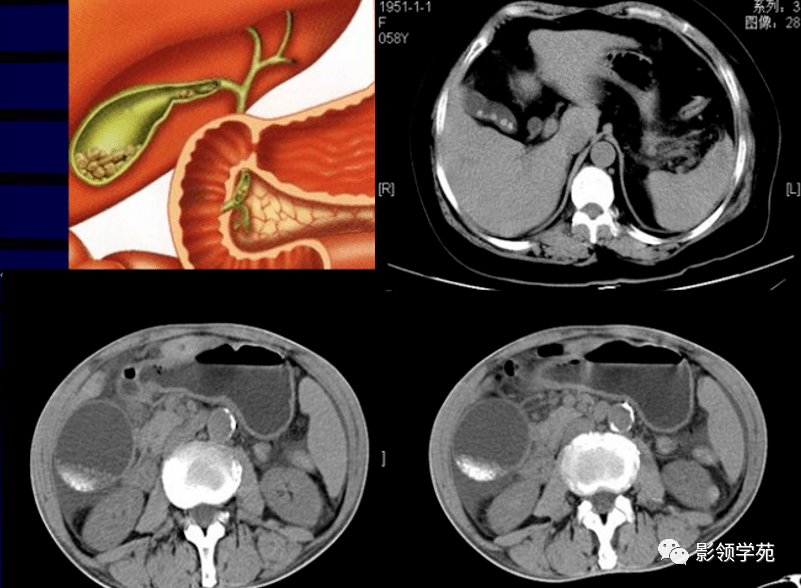

胆道系统疾病多层螺旋扫描ct诊断(一)

胆系结石上腹部ct平扫胆囊

急腹症影像:胆道结石ct表现!

肝内胆管结石 亳州市人民医院 影像中心